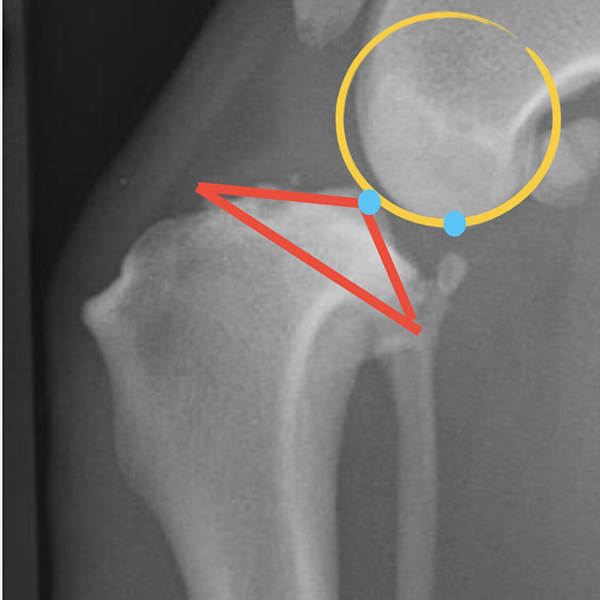

X線検査

レントゲン検査では、大腿骨と脛骨の位置関係や関節包の腫れ、腫瘍性疾患の存在を示唆する骨吸収像の有無などを確認します。写真の○と△は大腿骨と脛骨の位置関係を示しています。正常な位置関係では△の青丸と○の青丸が重なるように位置していますが、靭帯断裂症例では、両者の青丸がズレていることが確認できます。